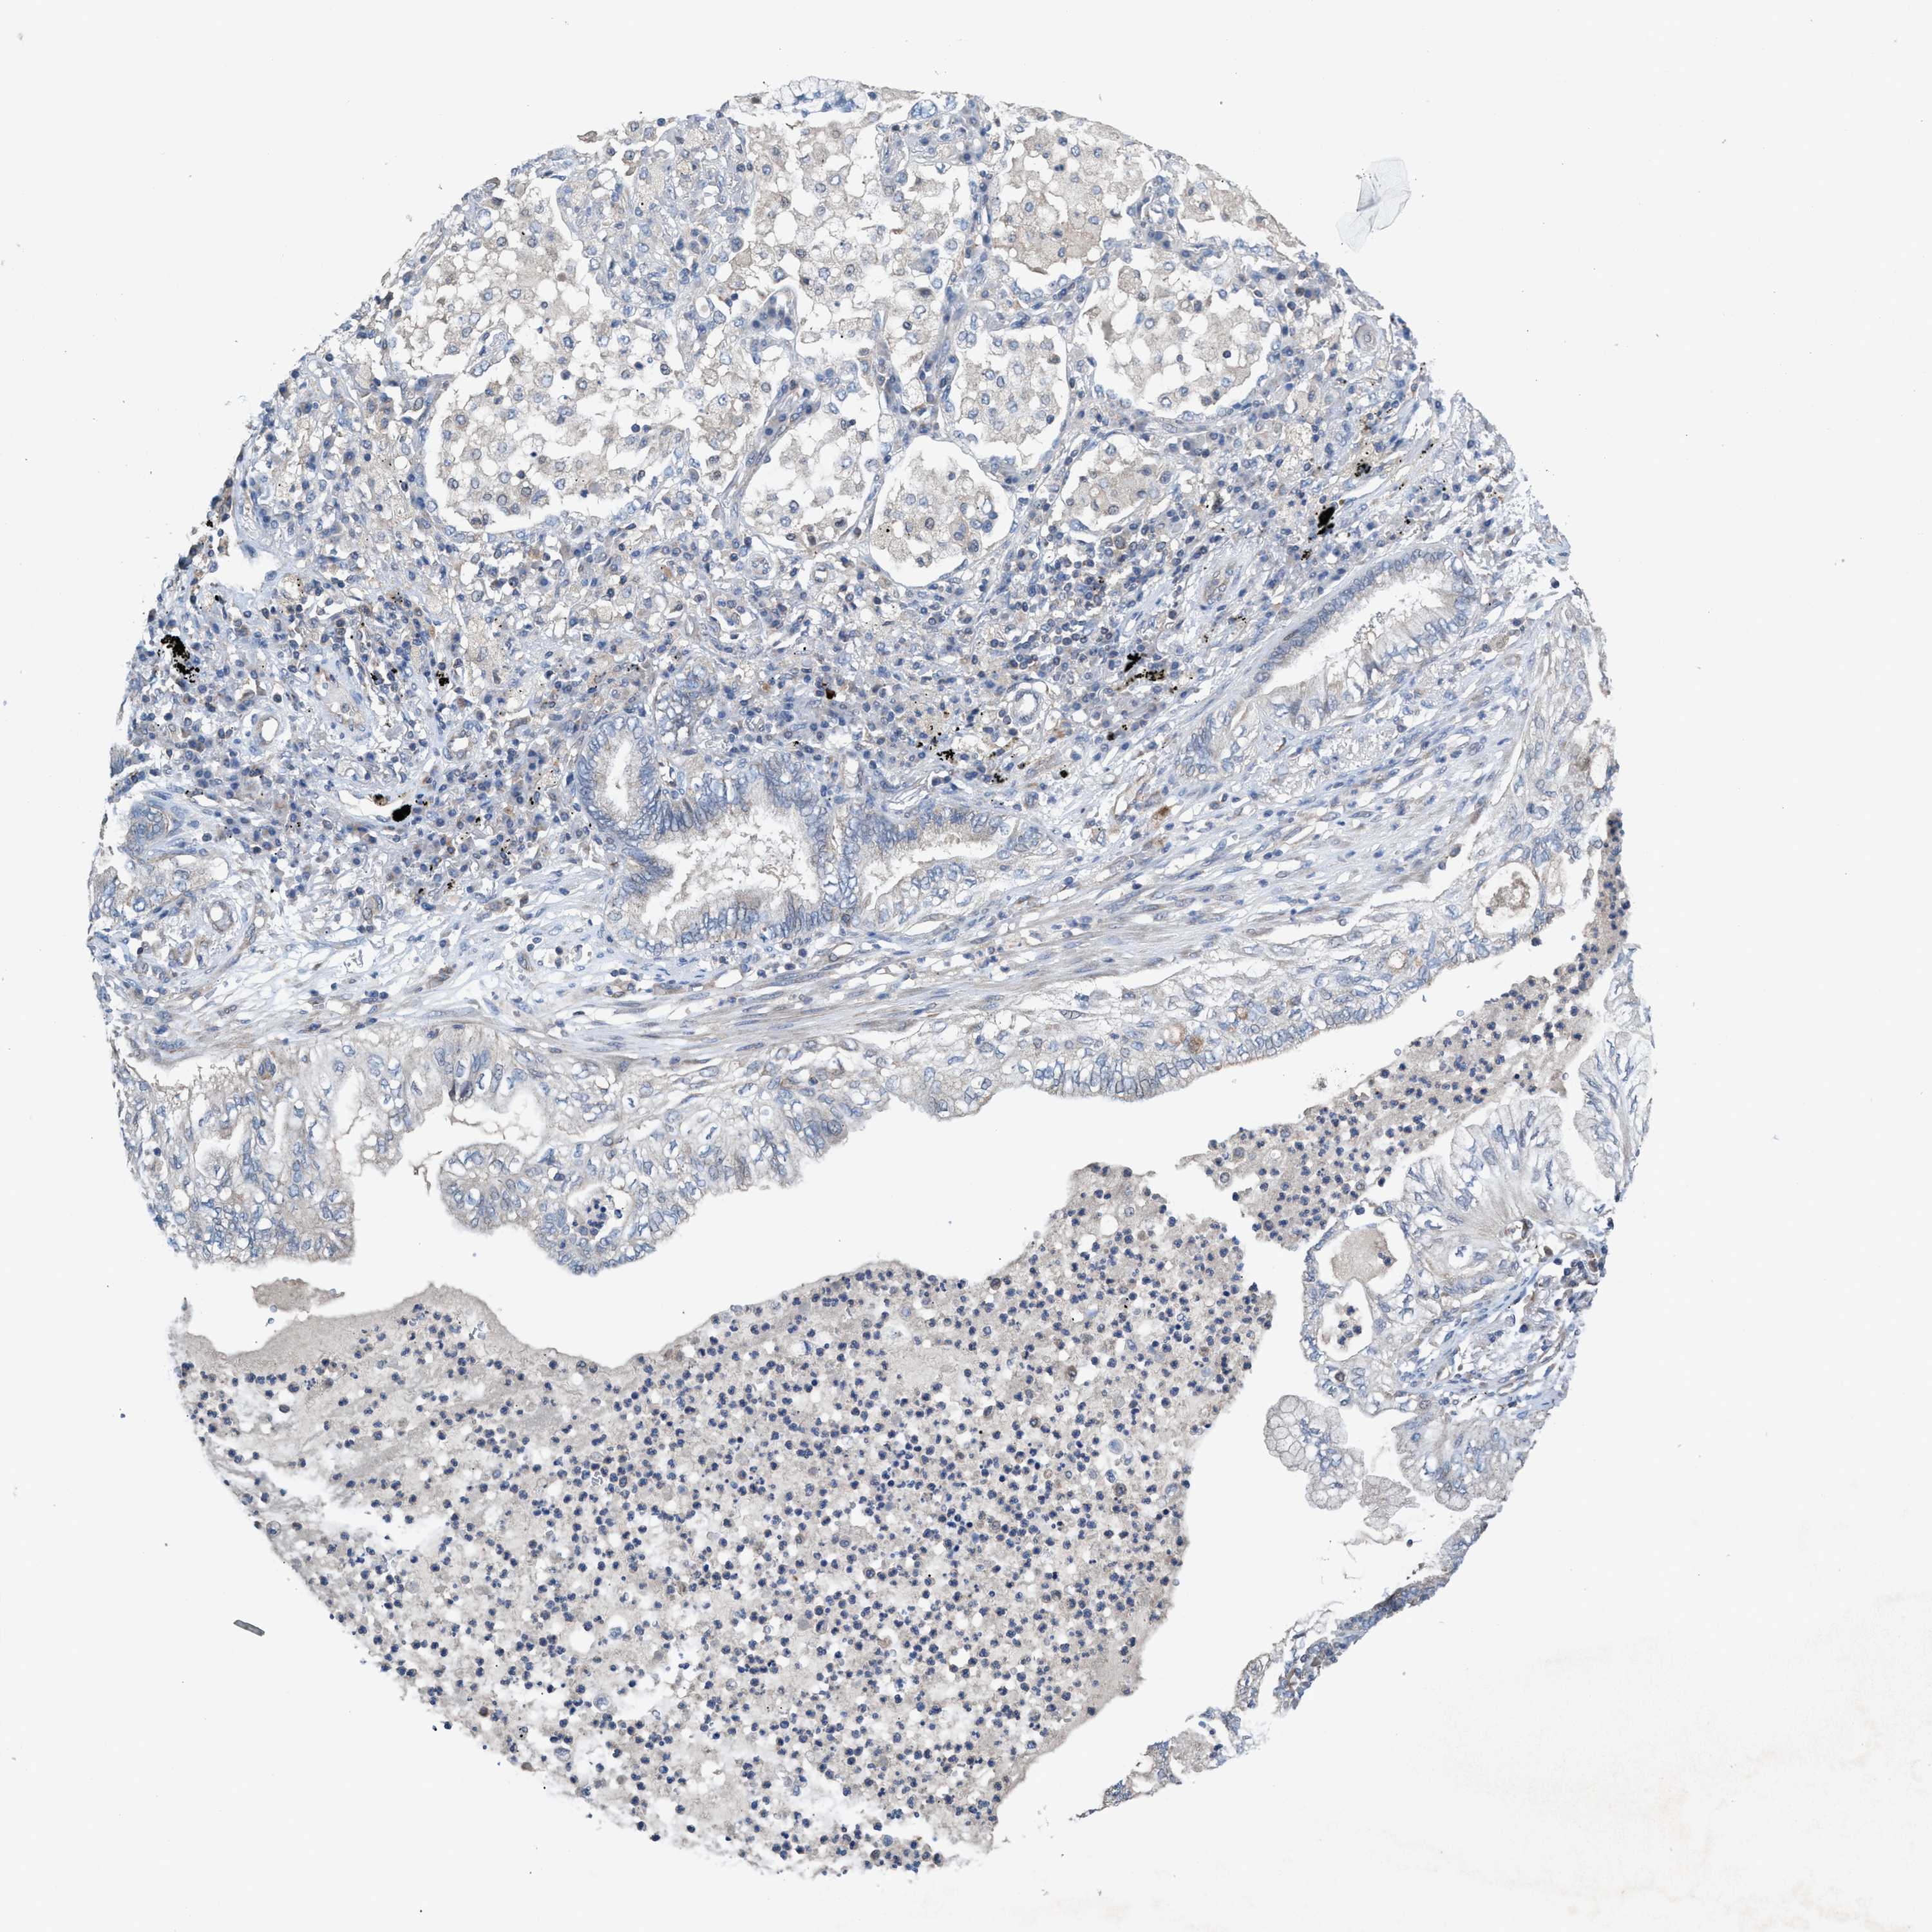

CANCER LUNG CANCER Show tissue menu

LUAD TCGA LUAD VALIDATION LUSC TCGA LUSC VALIDATION PROTEIN LUAD CPTAC PROTEIN LUSC CPTAC PROTEIN EXPRESSION

ANTIBODIES

AND

VALIDATION